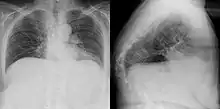

Gibbus deformity is a form of structural kyphosis typically found in the upper lumbar and lower thoracic vertebrae, where one or more adjacent vertebrae become wedged. Gibbus deformity most often develops in young children as a result of spinal tuberculosis and is the result of collapse of vertebral bodies.[1][2][3] This can in turn lead to spinal cord compression causing paraplegia.[4][5]

Gibbus deformity is included in a subset of structural kyphosis that is distinguished by a higher-degree angle in the spinal curve that is specific to these forms of kyphosis. Other conditions within this subset include Pott's disease and Scheuermann kyphosis, but gibbus deformity is marked by an especially sharp angle. Viewed from behind, the resulting hunchback is more easily seen when bending forward.[10] A kyphosis of >70° can be an indication of the need for surgery and these surgeries can be necessary for children as young as two years old, with a reported average of 8 years of age.[9]